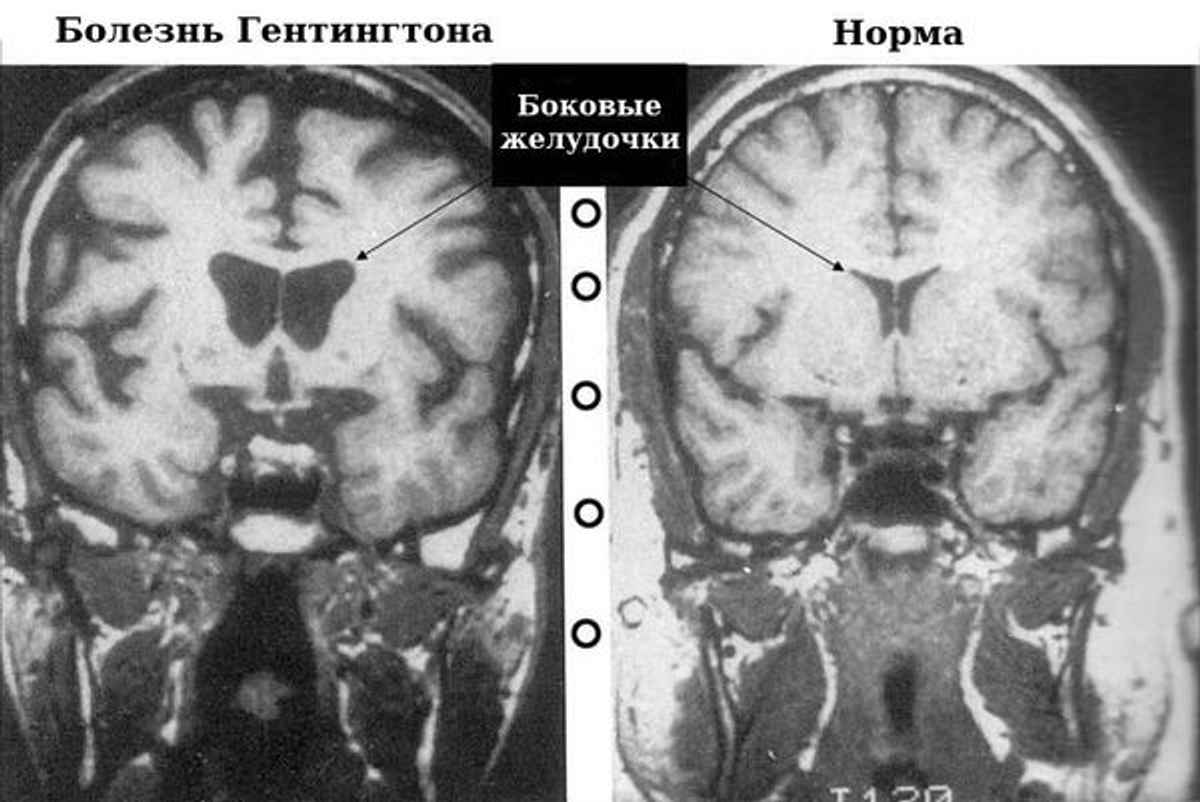

Болезнь вызывает мутация белка гентингтина, которая начинает убивать клетки мозга, вызывая изменения когнитивных способностей и хорею — беспорядочные, неконтролируемые движения. Человек может испытывать проблемы с узнаванием других людей и не понимать, сыт он или голоден, у него появляются проблемы с памятью. Болезнь передается по наследству с вероятностью 50%.